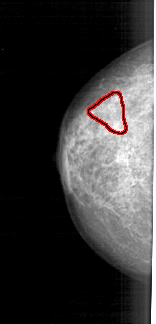

A_1723_1.LEFT_MLO

LEFT_MLO LINES 5461 PIXELS_PER_LINE 2356 BITS_PER_PIXEL 12 RESOLUTION 43.5 OVERLAY

FILE: A_1723_1.LEFT_MLO.OVERLAY

TOTAL_ABNORMALITIES 1

ABNORMALITY 1

LESION_TYPE CALCIFICATION TYPE PLEOMORPHIC DISTRIBUTION SEGMENTAL

ASSESSMENT 4

SUBTLETY 3

PATHOLOGY MALIGNANT

TOTAL_OUTLINES 1

BOUNDARY